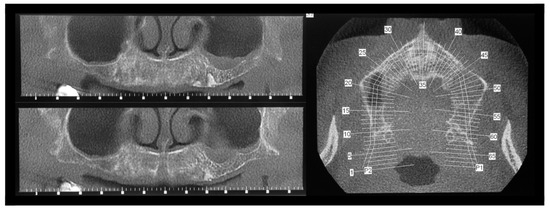

Figure 1. A 67-year-old woman presenting a fixed bridge in the upper maxilla from left second premolar to right canine: pre-operative frontal (a) and occlusal (b) clinical view; periapical X-rays of the upper maxillary elements (c): see multiple endodontic lesions. As visible from the radiographs, “hopeless” sites needed for extraction were 5, but the surgeon considered the extractions of all superior teeth for long-term prosthetic rehabilitation requirements.